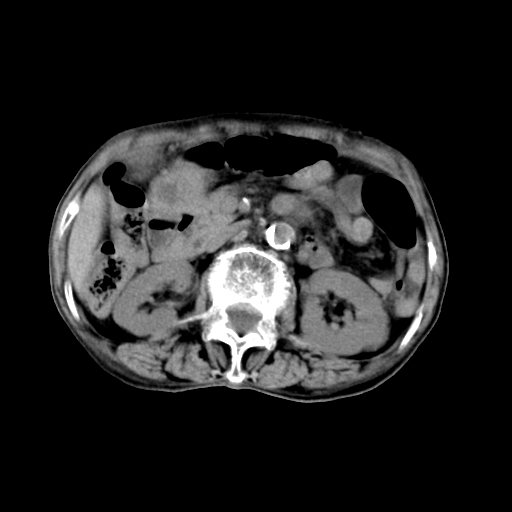

标题: CT19149:女,68岁,腹胀、恶心两周。 [打印本页]

标题: CT19149:女,68岁,腹胀、恶心两周。

女,68岁,腹胀、恶心两周,先做ct平扫,当时家属不同意强化,6天后家属要求增强扫描。

不均匀脂肪肝,胃腔改变须结合钡餐或胃镜观察

1)局灶性脂肪肝。2)胃窦癌可能,建议行胃镜检查。